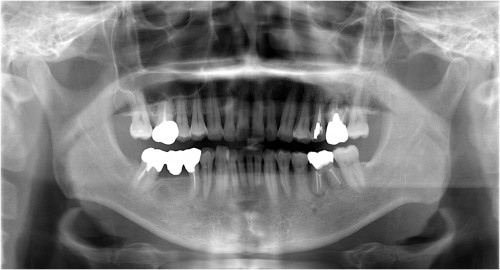

インプラント埋入直前

被せ物装着後